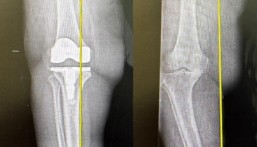

تمكّن مستشفى الدكتور سليمان الحبيب بالخبر، من إنهاء معاناة مراجع يبلغ من العمر “22” عاماً، كان يعاني من جلطات وريدية حادة في الأوردة العميقة للطرف السفلي الأيسر، وسببت أعراضاً حادة، وأُجريت له عملية متقدمة بتقنية شفط التخثرات بمساعدة الحاسوب الحديثة باستخدام جهاز penumbra lighting 12 المتقدمة، ذكر ذلك د.أحمد تايه استشاري جراحة الأوعية الدموية والقسطره العلاجية ورئيس الفريق الطبي المعالج.

وأوضح د. أحمد أن المراجع وصل إلى المستشفى وهو يعاني من حزمة أعراض حادة، أبرزها تورم وآلام شديدة في الساق اليسرى، بالإضافة إلى تغير لون جلد الطرف السفلي الأيسر. وقد أثارت هذه الأعراض الشكوك حول وجود جلطات وريدية عميقة، الأمر الذي دفع الفريق الطبي إلى إجراء حزمة من الفحوصات الدقيقة لتأكيد التشخيص، وشملت تحليل الدم للكشف عن المؤشرات الدالة على وجود الجلطات، بالإضافة إلى تصوير Ultrasound، لتقييم تدفق الدم عبر الأوردة واكتشاف التجلطات، كما تم استخدام التصوير بالأشعة المقطعية لتحديد مدى انتشارها بدقة، حيث أكدت النتائج وجود تخثرات في الأوردة العميقة للطرف السفلي الأيسر، أدت إلى تأثر الطرف بنقص التروية.

وأضاف د. أحمد أن الفريق الطبي درس الحالة ووضع خطة علاجية متكاملة، تضمنت إجراء تدخل طارئ بتقنية شفط التخثرات بمساعدة الحاسوب Computer Assisted Vacuum Thrombectomy ، باستخدام جهاز penumbra lighting 12، وتعد هذه التقنية من أحدث الأساليب الطبية لعلاج الجلطات الوريدية، وتم خلال العملية إذابة وشفط الجلطات من الأوردة المتضررة، ما ساعد ولله الحمد، على استعادة تدفق الدم بشكل طبيعي ومنتظم. وتحسنت حالة المراجع بعد العملية مباشرة، ومن ثم غادر المستشفى سيراً على قدميه بعد أيام قليلة دون أي مضاعفات. ولاحقاً أظهرت فحوصات فتح الأوردة، وعودة التروية الدموية إلى وضعها الطبيعي.

وأوضح د. أحمد أن الجهاز الذي استخدم في التدخل الطبي، يتميز بوجود حساس حاسوبي يمكنه من التمييز بين الدم والجلطات، ويقوم بشفط التخثرات فقط مما يقلل النزف، ويحد من احتمالات المضاعفات، ويعطي نتائج أفضل، إضافة إلى أن العملية تجرى تحت التخدير الموضعي.